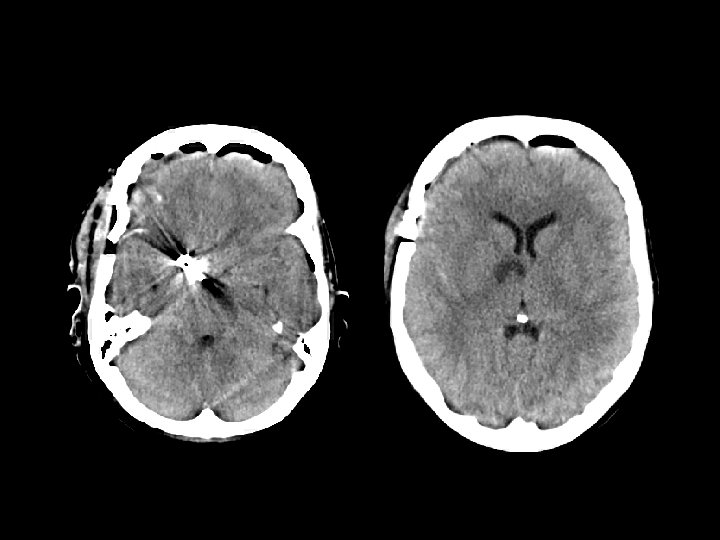

Anoxic Brain Injury • Findings: – Hypodense cerebral hemispheres with effacement of cortical gyri – Relative sparing of cerrebellum • Due to global insult: – Profound hypotension – Carbon monoxide poisoning • MRI findings: – Dense basal ganglia